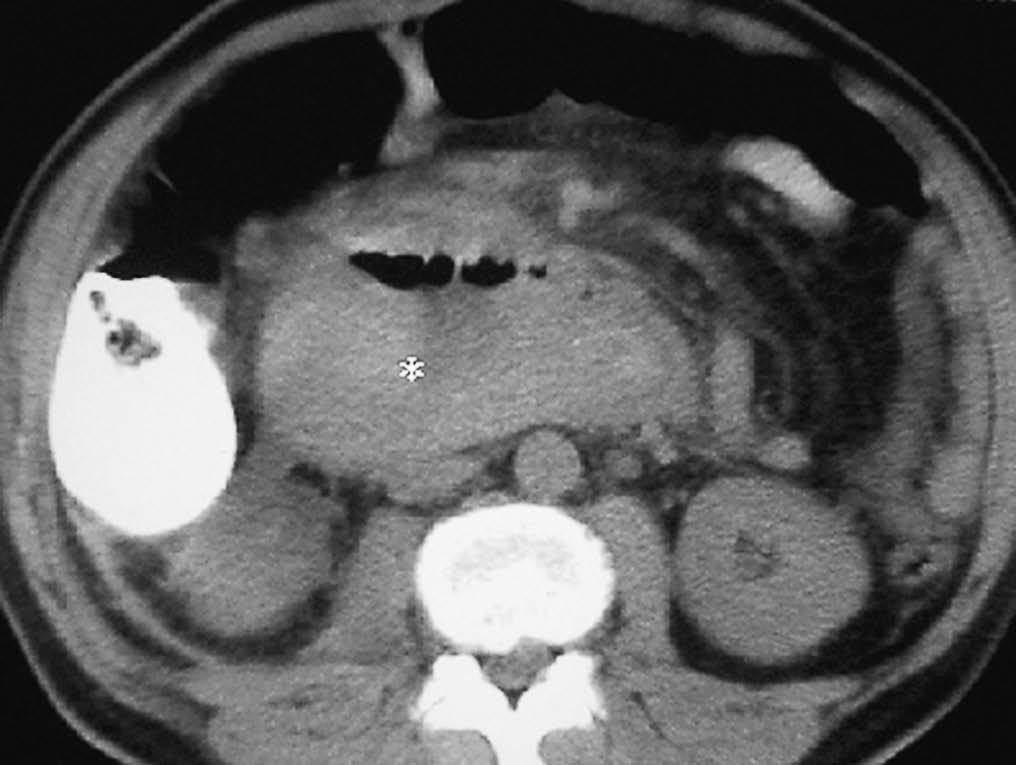

La causa más frecuente es la pancreatitis. Las enzimas pancreáticas pueden provocar una inflamación parietal del duodeno y estenosis de su luz. En procesos severos el componente inflamatorio llega a erosionar los vasos sanguíneos produciendo hemorragia duodenal e incluso puede provocar necrosis y perforación duodenal17 (fig. 10).

Fig. 10--Hematoma duodenal secundario a pancreatitis. (A) Colección líquida (flechas) en la pared del duodeno con aspecto quístico en la ecografía. AO: Aorta; VCI: vena cava inferior. (B) En la tomografía computarizada sin contraste intravenoso el hematoma (*) se observa como una colección hiperdensa en la pared duodenal.